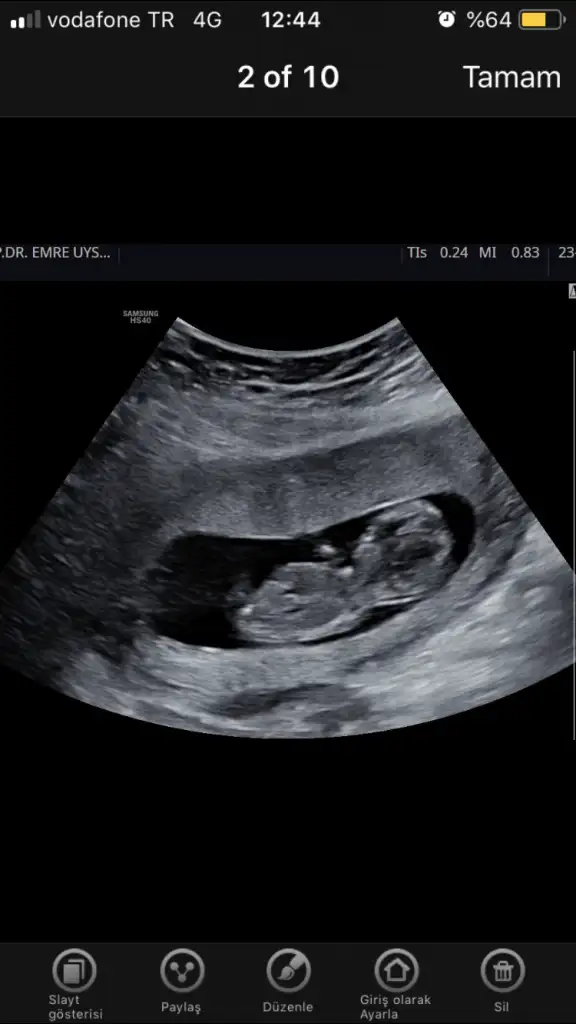

Erkek diyorumKızlar herkese selammmbiz 11+2 yiz bugün

nedir cinsiyet tahminleriniz rica etsek bakar mısınız bizim görüntülerimize de

Kaç haftalık burda tam görünmüyor nub altı paralel geliyor yanılmıyorsam kız bu minnoşArkadaşlar merhaba ben de 13 haftalik hamileyim doktor yanilma payını düşünerek suan belirtmedi cinsiyetini yorumlarsaniz sevinirim. Tabi hic önemi yok cinsiyetin ama bir haftadir aşırı merak içindeyim:)) hepimize saglikla kucağına almayi nasip etsin

Canım teşekkürler öncelikle cevabin icin:) 13+3 o fotoğraftaKaç haftalık burda tam görünmüyor nub altı paralel geliyor yanılmıyorsam kız bu minnoş